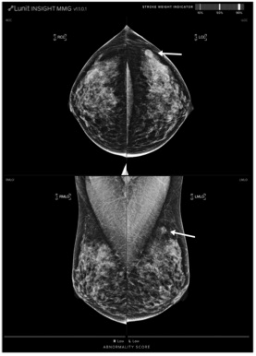

一位44歲的患者被診斷為左乳有一個20毫米大小的三陰性亞型浸潤性導管癌,分期為T1cN0。左側乳腺癌在1點鐘方向表現為腫塊(箭頭),被AI-CAD遺漏(異常評分7分)